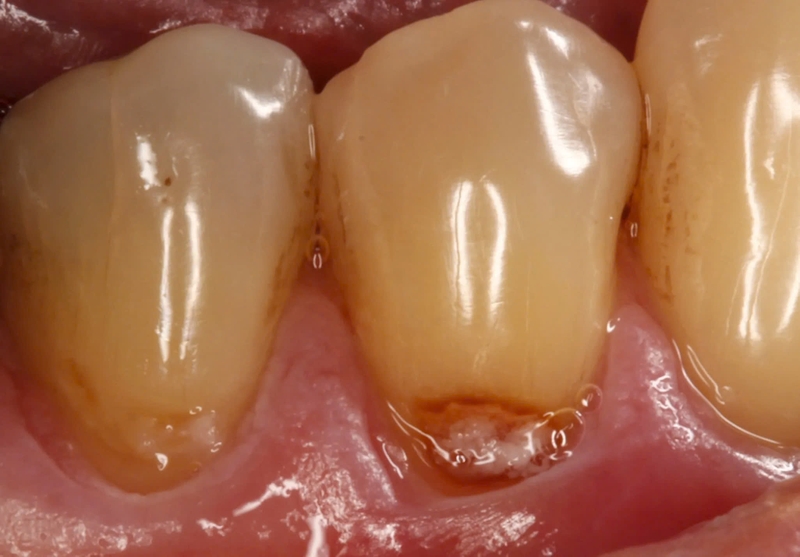

Sâu chân răng là một vấn đề răng miệng phổ biến nhưng thường bị bỏ qua cho đến khi gây đau nhức hoặc biến chứng nghiêm trọng. Nếu không được phát hiện và điều trị kịp thời, sâu chân răng có thể gây viêm nhiễm, mất răng và ảnh hưởng đến sức khỏe toàn thân. Hãy cùng chúng tôi tìm hiểu chi tiết hơn về sâu chân răng và một số thông tin liên quan nhé!

Sâu chân răng là một trong những vấn đề răng miệng phổ biến nhưng thường bị bỏ qua cho đến khi gây ra đau nhức hoặc biến chứng nghiêm trọng. Tình trạng này xảy ra khi vi khuẩn trong mảng bám răng tấn công men răng và lan xuống phần chân răng, gây tổn thương cấu trúc răng và nướu. Tuy nhiên, bệnh lý này hoàn toàn có thể phòng ngừa bằng cách duy trì vệ sinh răng miệng đúng cách và thay đổi thói quen ăn uống. Vậy đâu là nguyên nhân chính gây sâu chân răng, những hậu quả có thể gặp phải và làm thế nào để bảo vệ răng hiệu quả?

Sâu chân răng là một vấn đề răng miệng phổ biến có thể gây đau nhức, viêm nhiễm và ảnh hưởng nghiêm trọng đến sức khỏe răng miệng nếu không được điều trị kịp thời. Tình trạng này thường bắt đầu từ sự tích tụ mảng bám vi khuẩn, nhưng còn có nhiều yếu tố khác góp phần làm tăng nguy cơ sâu chân răng mà không phải ai cũng biết. Dưới đây là một số yếu tố gây nên tình trạng sâu chân răng.